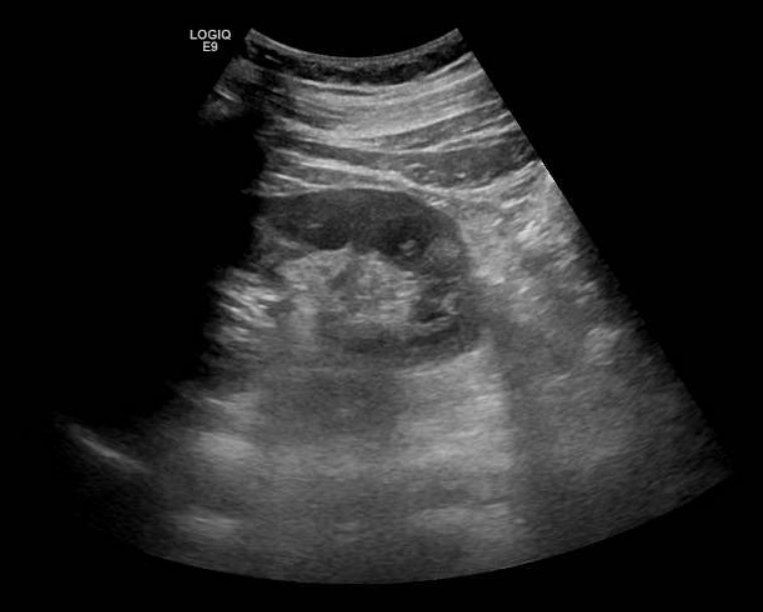

Se solicita ecografía abdominal que muestra líquido en espacio pararrenal posterior derecho bajo, sobre músculo psoasilíaco derecho, y leve ectasia piélica derecha sin identificar causa.

Entre las entidades que afectan al espacio pararrenal nos encontramos linfangioma, entidades fibróticas, hematomas, abscesos, neoplasias… Por tanto, se completa estudio con TAC abdominal con contraste. En el TAC se observa litiasis de 3 mm en meato ureteral derecho con dilatación pielocalicial grado II y leve-moderada cantidad de líquido en espacios retroperitoneales peri y pararrenal derechos, que se relacionan con salida de contraste intravenoso en fase excretora, compatible con rotura de la vía urinaria sin identificarse claro punto de fuga.